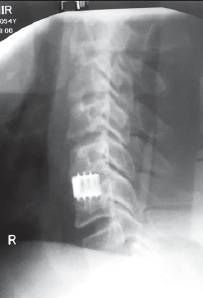

Если у пациента грыжа крупных размеров, то ему проводят классическую операцию — дискэктомию. В ходе неё хирург удаляет весь поражённый диск или его часть открытым доступом, т. е. через обычные разрезы на теле. Затем на место удалённого пульпозного ядра помещается имплант.

![Рентген-снимок позвоночника после дискэктомии. С5–С6 сегменты фиксированы титановым имплантом [12] Рентген-снимок позвоночника после дискэктомии. С5–С6 сегменты фиксированы титановым имплантом [12]](/media/bolezny/shejnaya-gryzha/rentgen-snimok-pozvonochnika-posle-diskektomii-s5_s6-segmenty-fiksirovany-titanovym-implantom-12_s.jpeg)

Рентген-снимок позвоночника после дискэктомии. С5–С6 сегменты фиксированы титановым имплантом [12]

Такие операции, как правило, требуют более длительного восстановления: от нескольких месяцев до полугода. В первые недели пациенту рекомендуется избегать резких движений и физических нагрузок, особенно нужно беречь руки. При этом следует выполнять все упражнения, назначенные врачом, для укрепления мышц шеи и спины. В это время пациент носит сначала жёсткий пластмассовый, а затем мягкий поролоновый воротник.